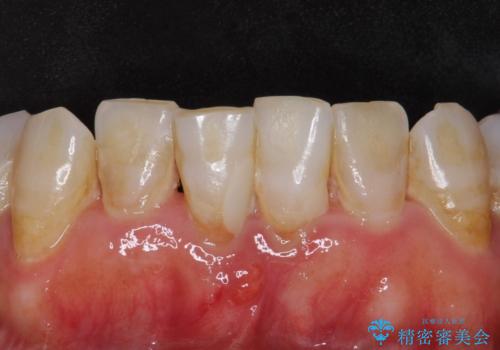

口腔内を精査したところ、右上のブリッジの内側(口蓋側)がかけており、下の前歯(右下1)には唇舌側に瘻孔を伴う大きな根尖病変ができていました。

右上のブリッジ(右上④3②)のやりかえと、下の前歯(右下1)の根管治療を行った後セラミッククラウンによる補綴治療を行いました。

ブリッジとクラウンの自然な仕上がりと咬み心地に喜んで下さいました。

精密な根管治療により、下の前歯の歯ぐきにできていた瘻孔もなくなりました。